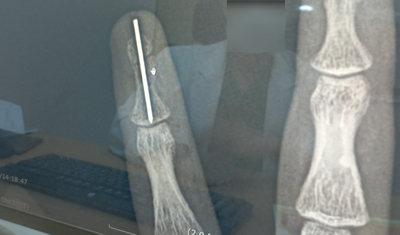

손가락 골절 수술 & 치료 후기

두달전에 일하다가 다쳤어요...ㅠㅜ 그래서 한동안 블로그 업뎃이 뜸했었어요.. 그것도 휴가 가기전 날 마...